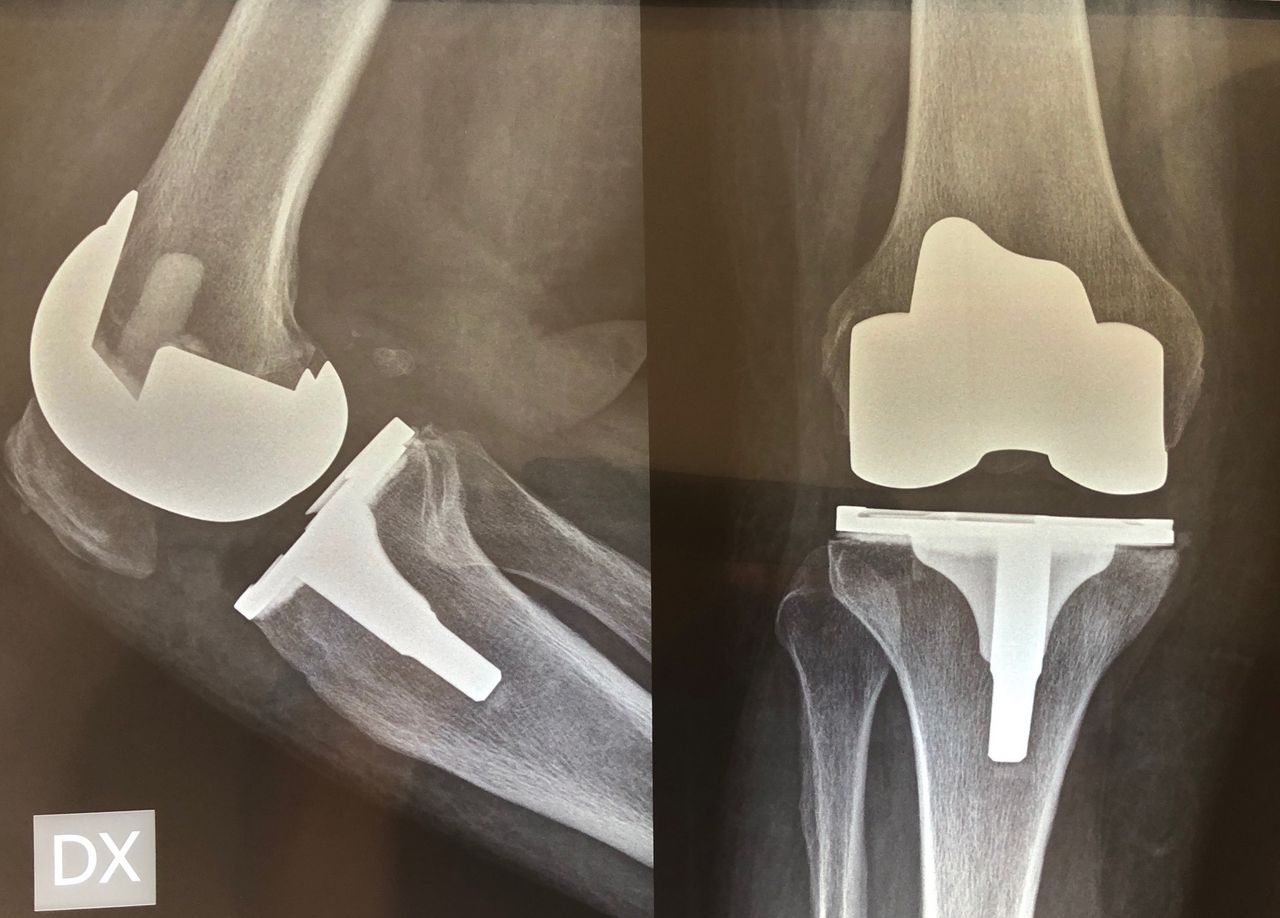

Sono specializzato nell'impianto di protesi di ginocchio ed anca in caso di patologie degenerative artritiche o necrotiche. Utilizzo protesi di ultima generazione, le protesi di ginocchio vengono applicate utilizzando una maschera creata su misura per ogni paziente, quelle di anca sono studiate per ridurre al minimo il rischio di lussazione (principale complicazione di questo tipo di intervento).

Salve, ho 54 anni e a giugno del 2019 ho fatto l'artoprotesi completa del ginocchio destro. Al controllo annuale ho fatto l'RX sotto carico in due proiezioni il cui referto è : "Protesi bicompartimentale apparentemente ben posizionata ed impiantata. Entesite calcifica del tendine quadricipitale".

Vorrei sapere se l'entesite si potrebbe risolvere in maniera spontanea o se è neccessario intervenire e come?